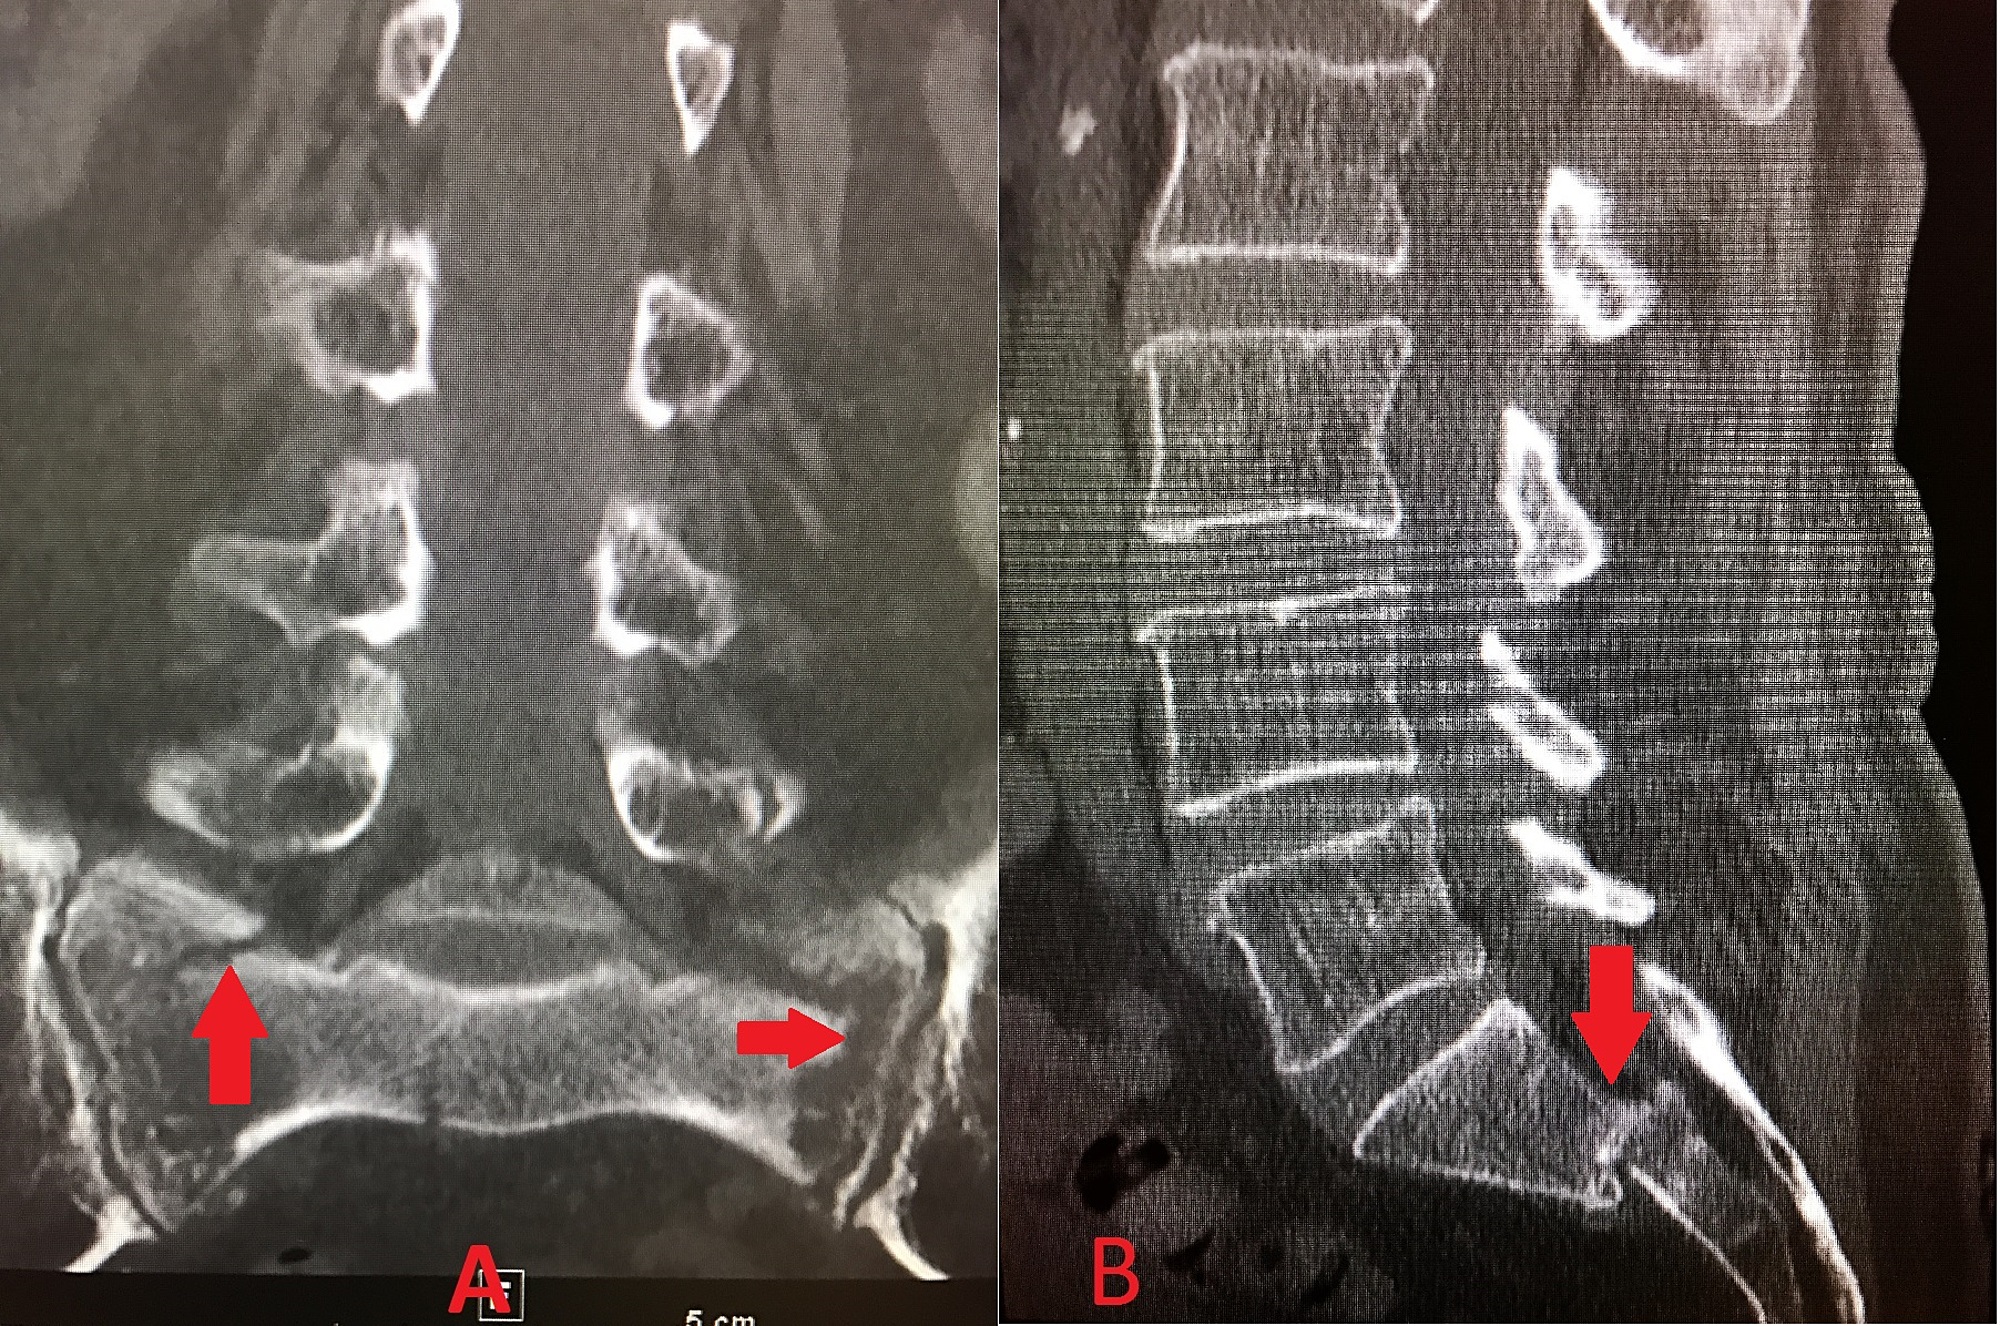

Percutaneous Sacroplasty for Sacral Insufficiency Fractures Case Fracture Sacrum Treatment — treatment for a sacral fracture if your sacrum is fractured, in most cases, treatment consists of rest, dr. A sacral fracture hurts, so you. — treatment may be nonoperative or operative depending on fracture displacement, associated pelvic ring instability and patient. — treatment for sacral insufficiency fractures can be a mix of noninvasive treatment and more. Fracture Sacrum Treatment.

Percutaneous Sacroplasty for Sacral Insufficiency Fractures Case Fracture Sacrum Treatment — considering these etiologies, the literature suggests sacral laminectomy to be a possible treatment to avoid sacral. — treatment for sacral insufficiency fractures can be a mix of noninvasive treatment and more invasive surgical procedures like. — treatment may be nonoperative or operative depending on fracture displacement, associated pelvic ring instability and patient. — treatment for. Fracture Sacrum Treatment.